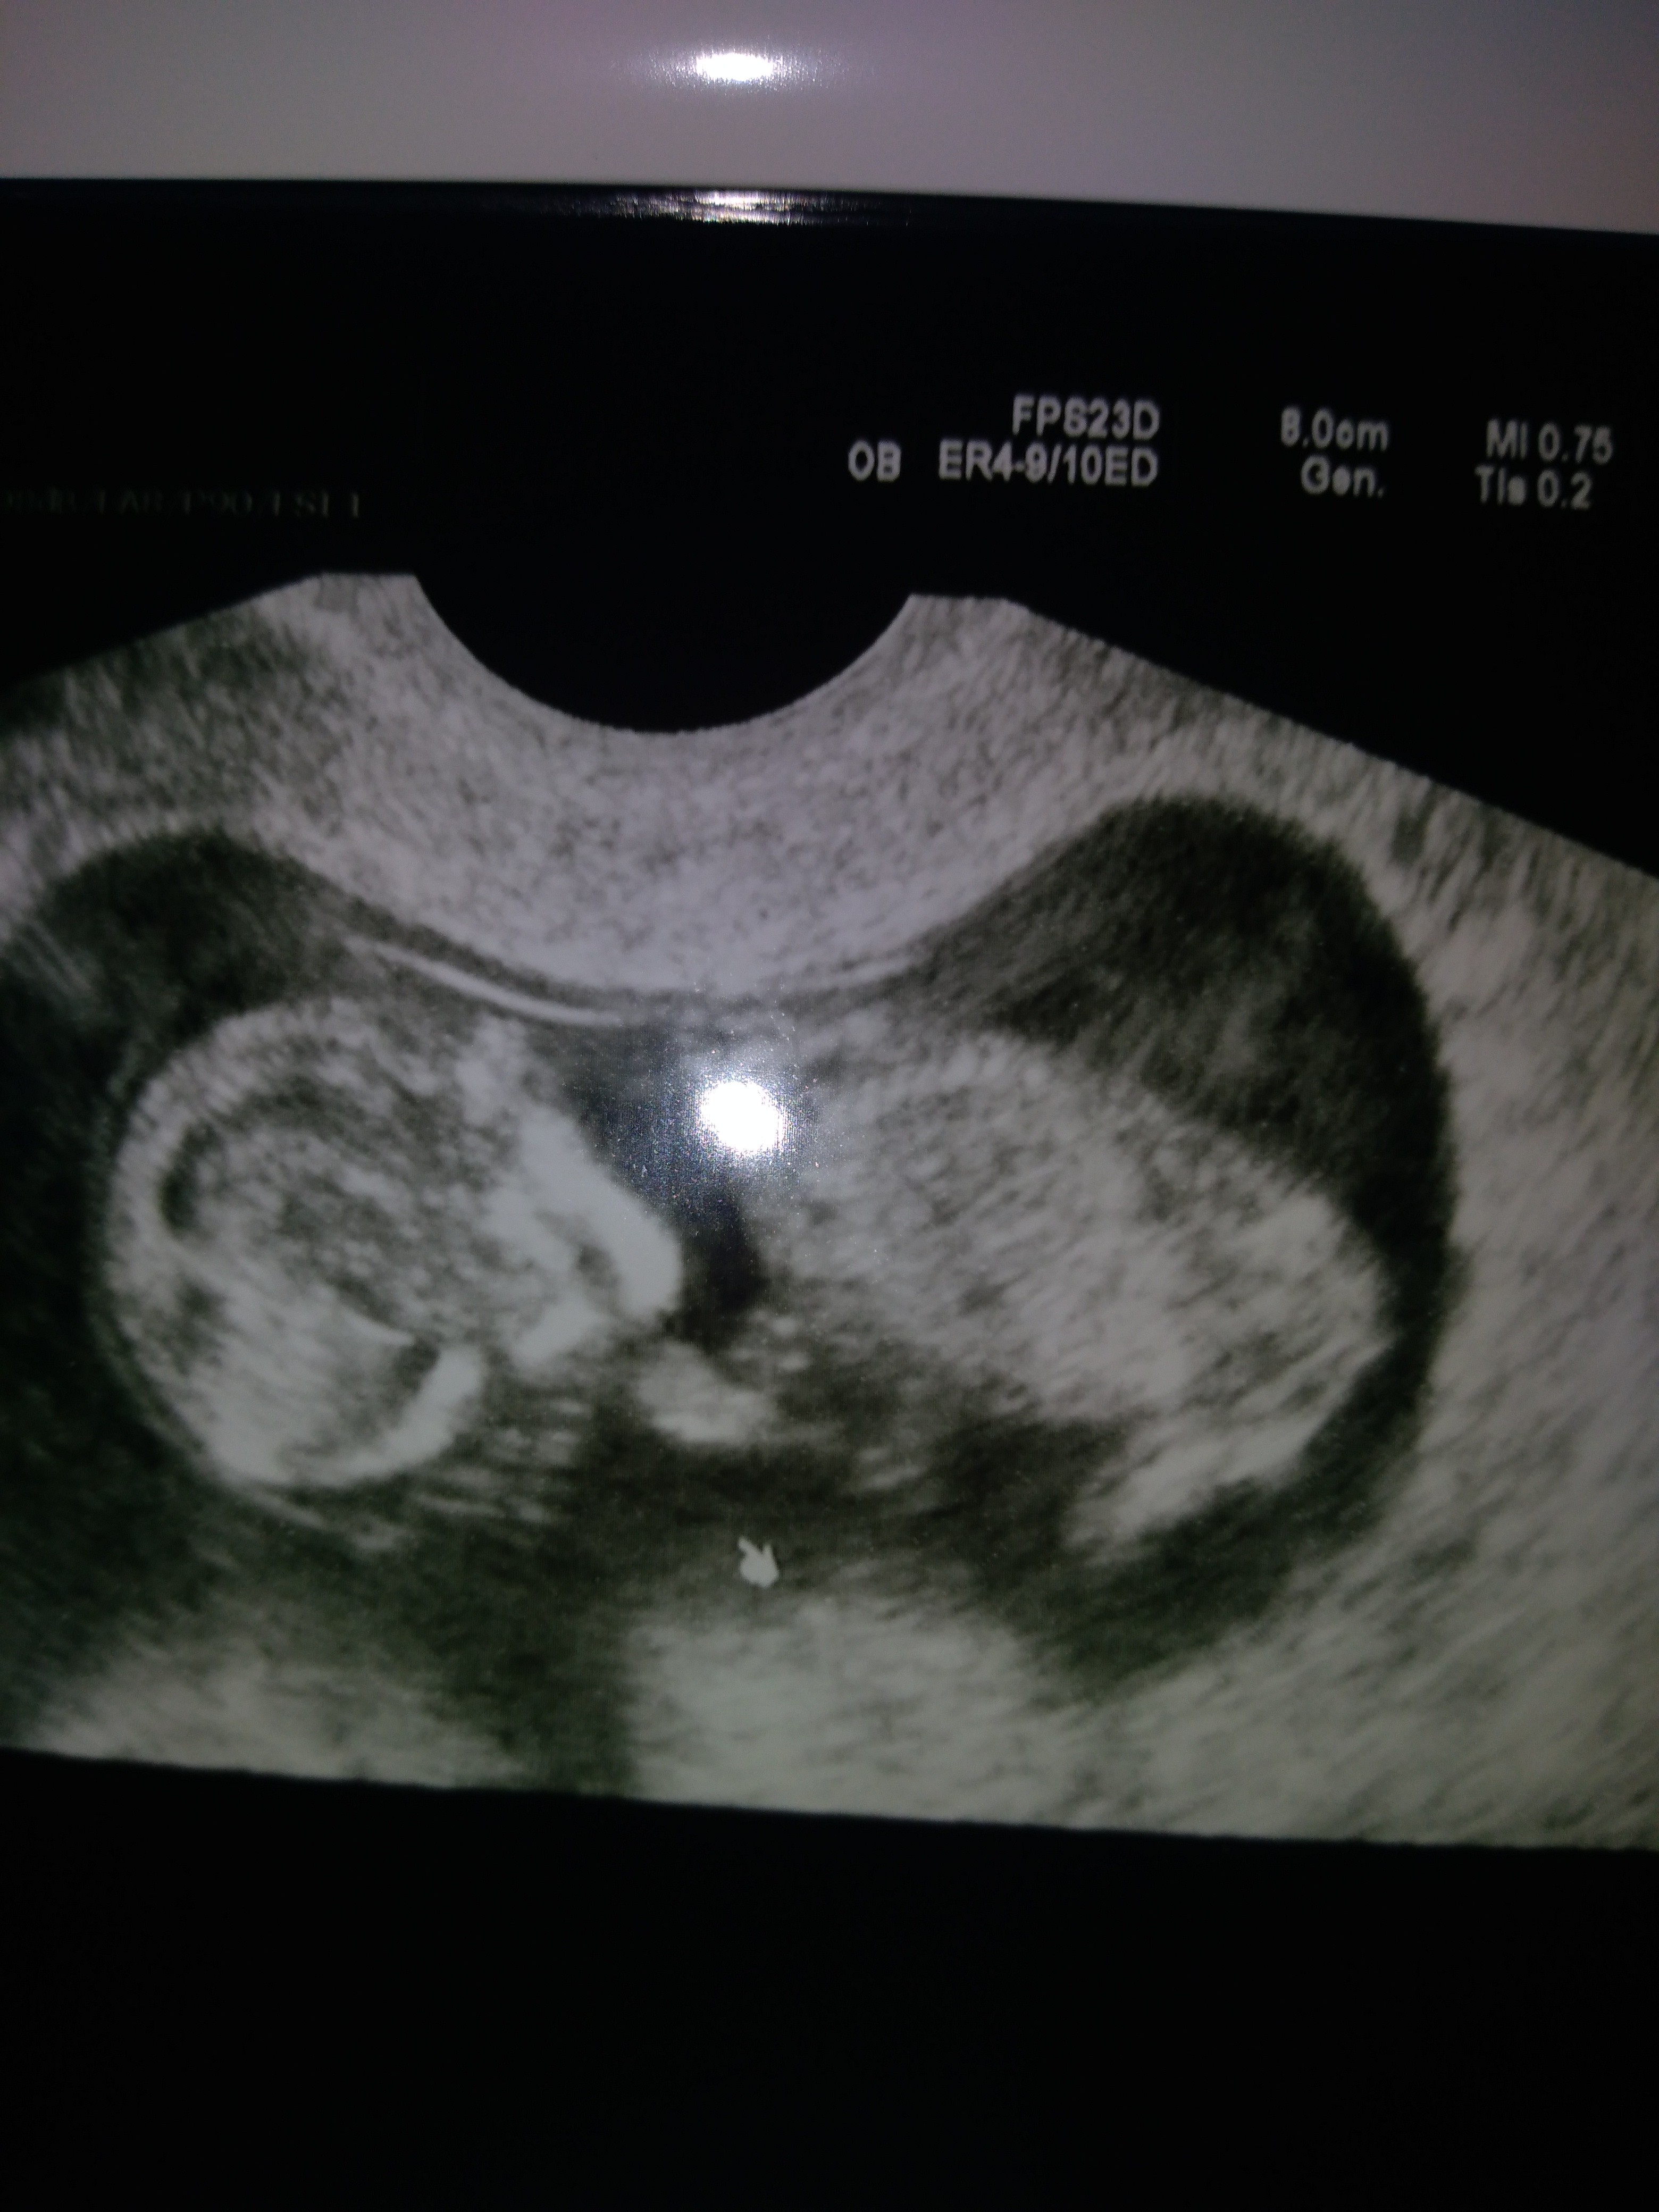

Wszystko ok, termin na 29.07. Bałwanek ma 13mm, serducho bije ładnie. Mam torbiel na jajniku sr.4cm, więc dostałam progesteron. Pobrał mi też cytologię.

To dobra wiadomość. Gratuluję. Przed poprzednią ciążą długo walczylam z torbielą a na półmetku ciąży już po niej śladu nie było. Twoja pewnie też się wchlonie.Wszystko ok, termin na 29.07. Bałwanek ma 13mm, serducho bije ładnie. Mam torbiel na jajniku sr.4cm, więc dostałam progesteron. Pobrał mi też cytologię.

Cudowna dzidzia. Bardzo się cieszę [emoji3590]I po wizycie 10 tydzień 5 dzień , z bąbelkiem wszystko jest dobrze. Jesteśmy mega szczęśliwi Zobacz załącznik 926240